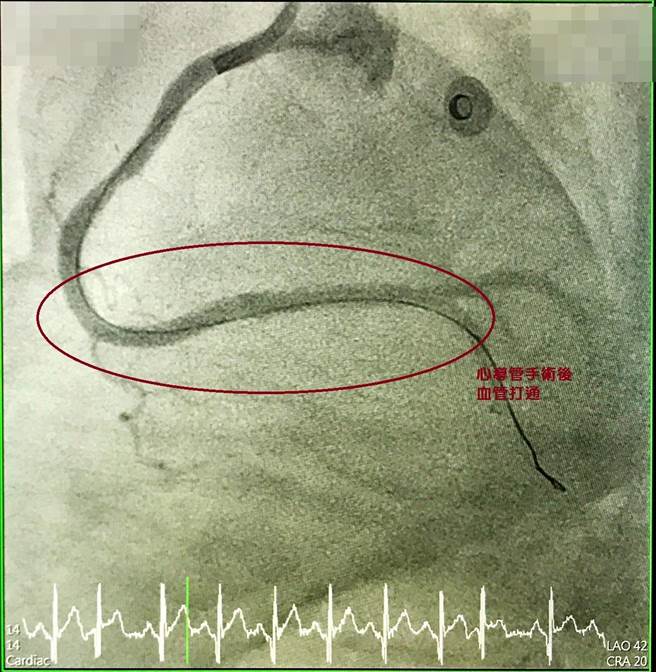

心導管手術後(血管已打通)。(大甲李綜合提供/陳淑娥台中傳真)